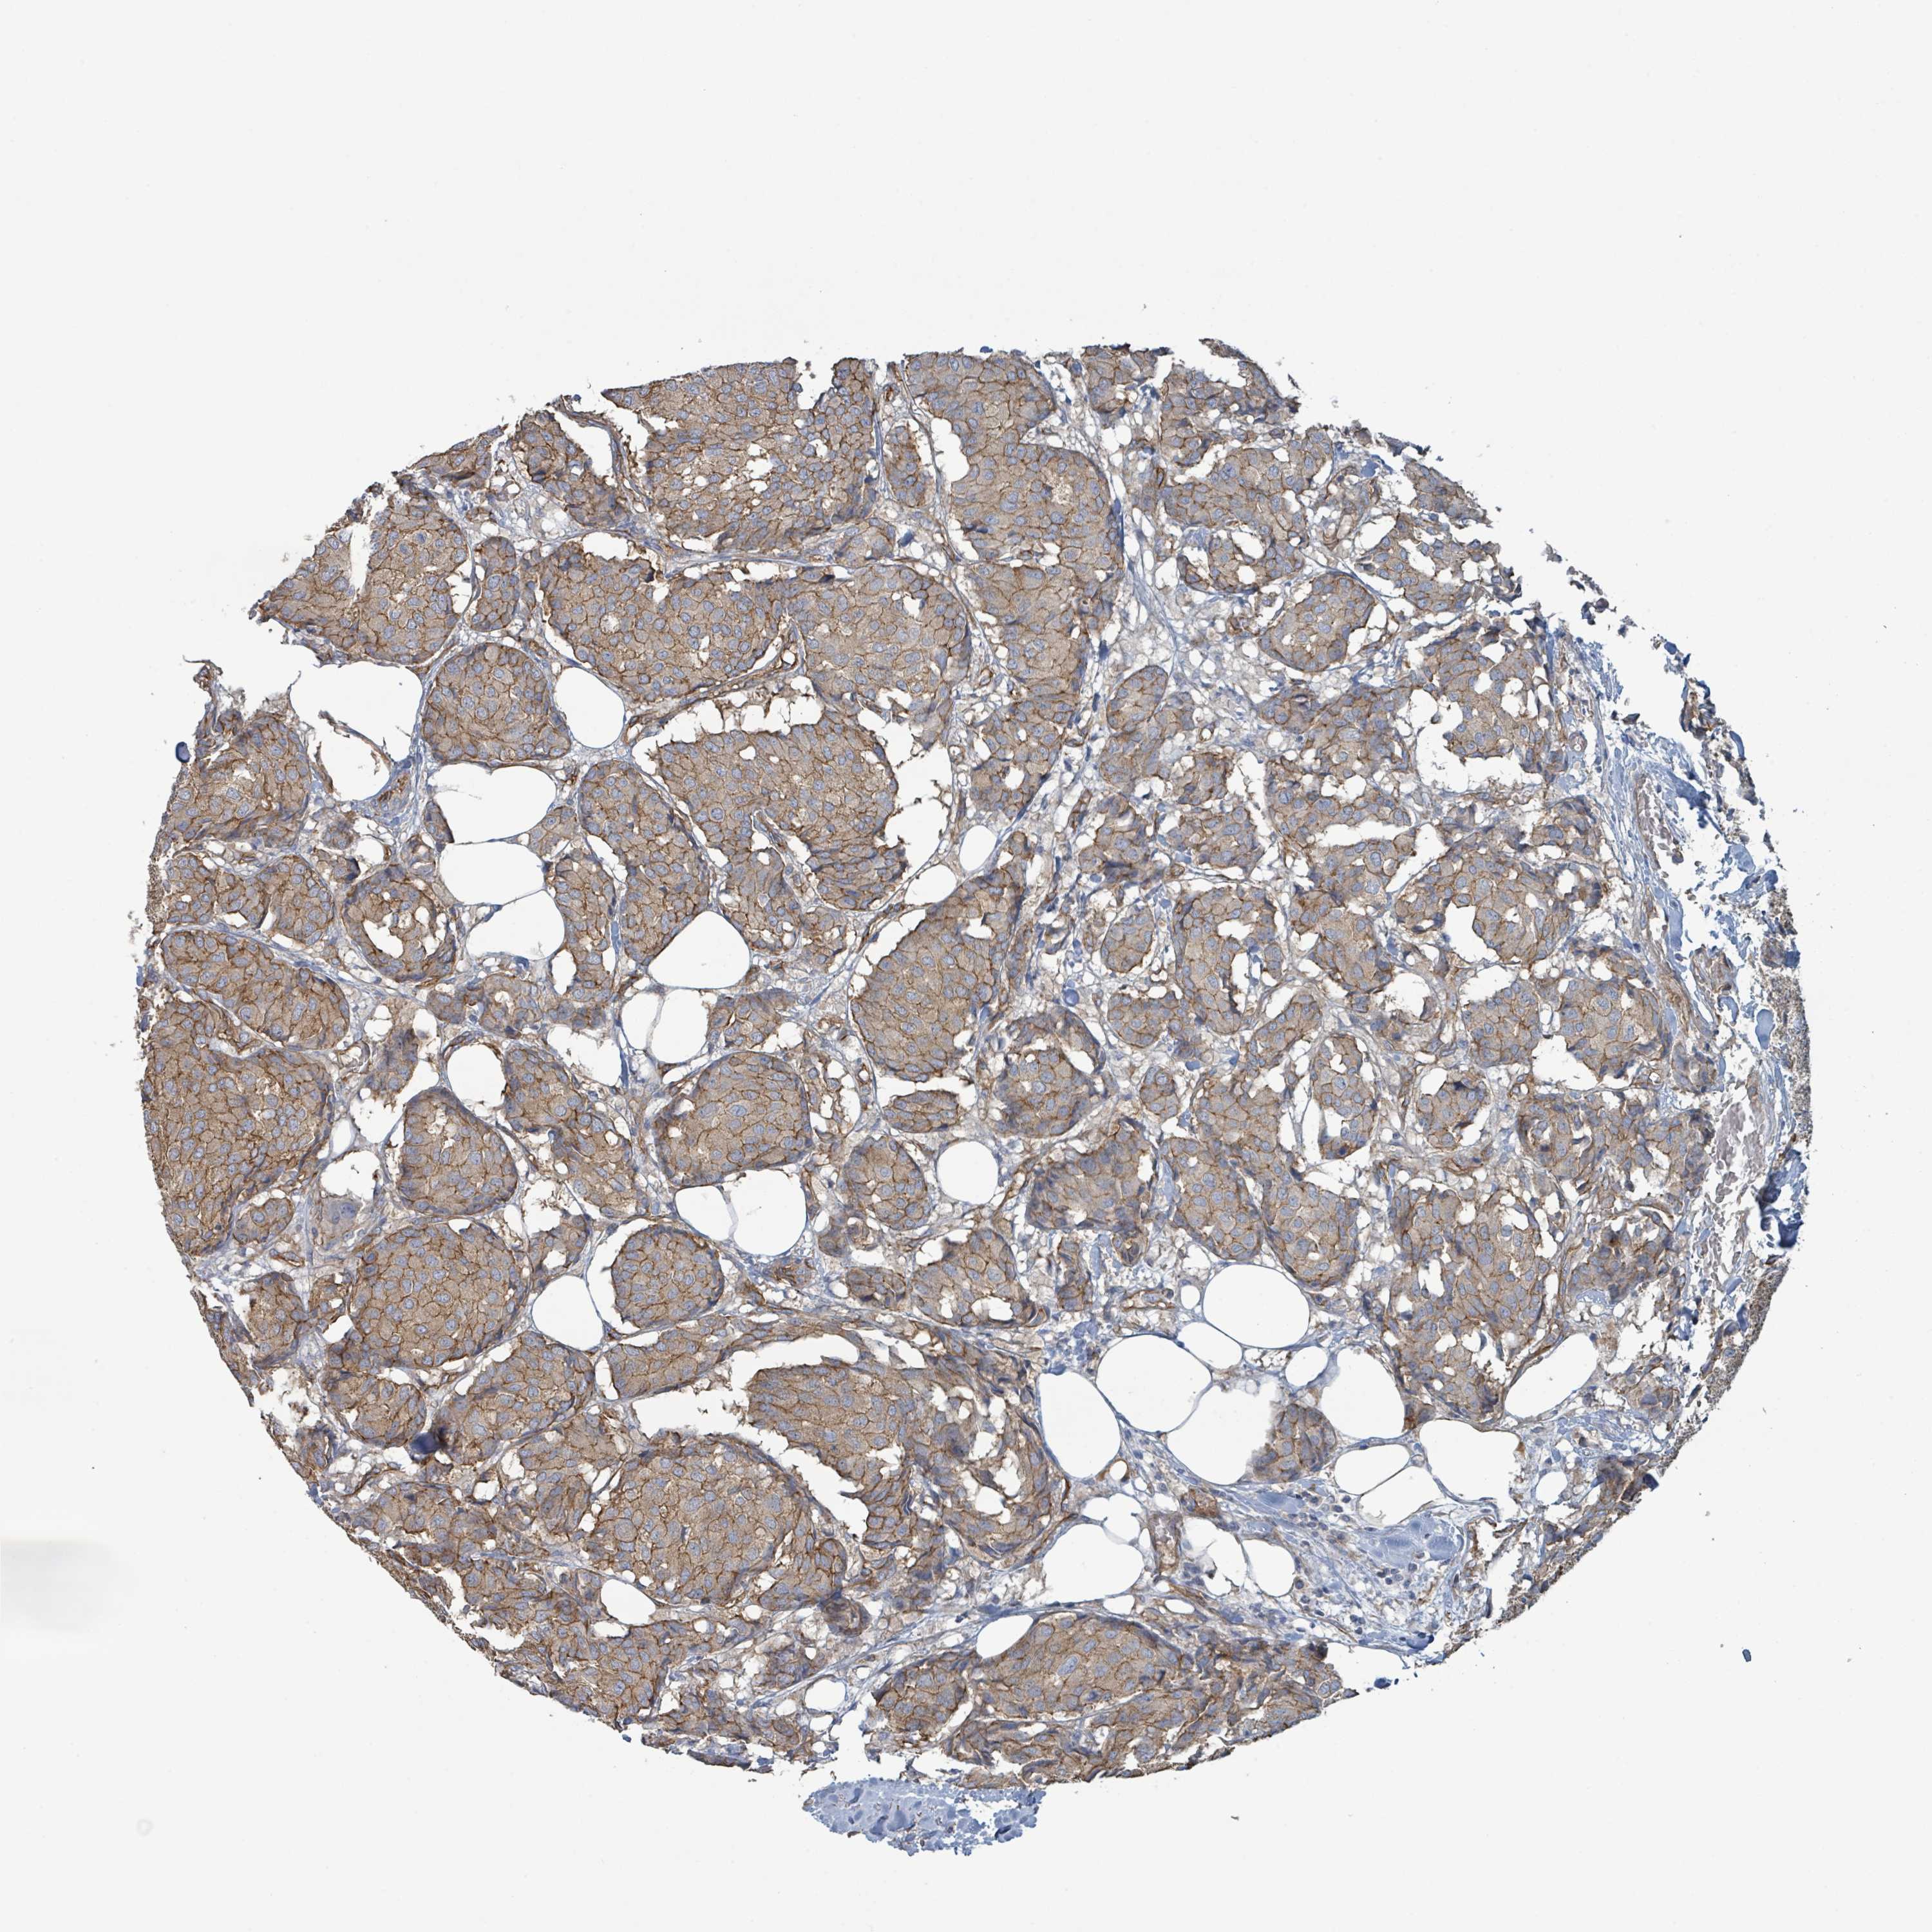

CANCER BREAST CANCER Show tissue menu

BRCA TCGA BRCA VALIDATION PROTEIN EXPRESSION